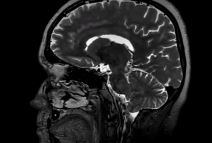

MLAD I ZDRAV ČOVEK SE SAMO SRUŠIO, POČEO DA BUNCA: Lekari zanemeli kada su na snimku videli GADOSTI koje mu žive u mozgu